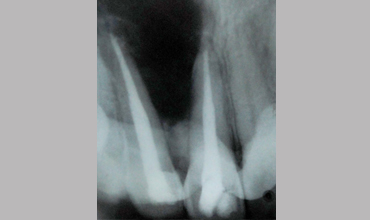

Surgical Management Of Large Periapical Cyst